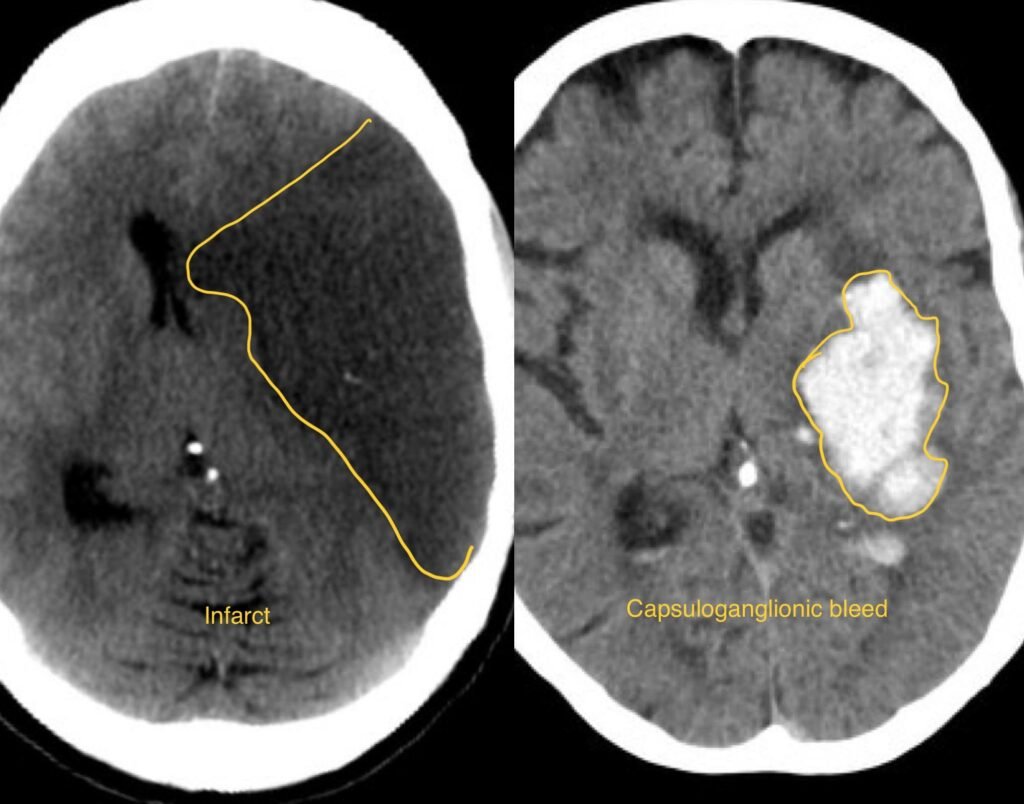

- Diagnosis of stroke typically involves a thorough neurological examination, medical history, imaging studies such as CT scans or MRI, and blood tests to evaluate blood clotting and other factors.

- Treatment options for stroke depend on the type and cause of the stroke but may include medications such as clot-busting drugs (thrombolytics), procedures to remove blood clots (mechanical thrombectomy), surgery to repair damaged blood vessels or remove plaque buildup (endarterectomy), and rehabilitation therapies such as physical therapy, occupational therapy, and speech therapy.